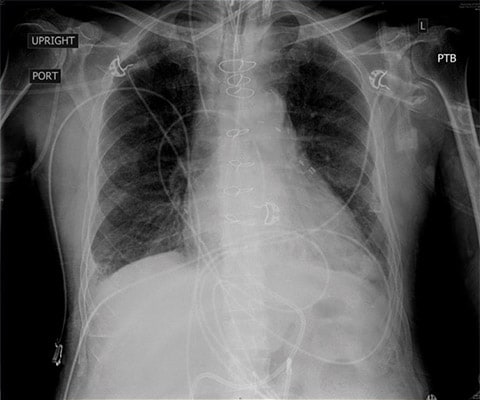

Biorąc pod uwagę niewydolność nerek pacjenta i oczekiwane ograniczenia w możliwości prowadzenia agresywnej terapii diuretykami zadecydowano o zaintubowaniu pacjenta w trybie ze wskazań nagłych, zwiększeniu dawki środków inotropowych oraz pogłębieniu prób wywołania diurezy za pomocą diuretyków. Jednocześnie podjęto rozmowy z rodziną pacjenta dotyczące możliwych opcji leczenia, w tym prawdopodobnej konieczności wdrożenia dializ. W czasie przygotowywania pacjenta do intubacji wykonano badanie RTG, które potwierdziło rozpoznanie obrzęku płuc.

Badanie POCUS przeprowadzone przy użyciu poręcznego urządzenia przenośnego umożliwiło wygodną i szybką ocenę pacjenta, postawienie rozpoznania oraz podjęcie interwencji u pacjenta prezentującego złożone objawy. Powtórne badanie RTG wykonane zaledwie godzinę po intubacji wykazało znaczną poprawę stanu obrzęku płuc.

Obraz CXR pozyskany przed intubacją przedstawiający rozlany, obustronny śródpęcherzykowy i śródmiąższowy obrzęk płuc.